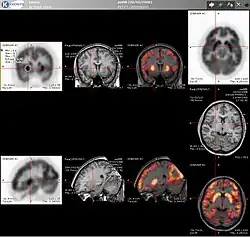

PET imaging with FDG takes advantage of the fact that the brain is normally a rapid user of glucose. Standard FDG PET of the brain measures regional glucose use and can be used in neuropathological diagnosis.

Brain pathologies such as Alzheimer's disease greatly decrease brain metabolism of both glucose and oxygen in tandem. Therefore FDG PET of the brain may also be used to successfully differentiate Alzheimer's disease from other dementing processes, and also to make early diagnoses of Alzheimer's disease. The advantage of FDG PET for these uses is its much wider availability. In addition, some other fluorine-18 based radioactive tracers can be used to detect amyloid-beta plaques, a potential biomarker for Alzheimer's in the brain. These include florbetapir, flutemetamol, Pittsburgh compound B (PiB) and florbetaben.[19]

Recent advances in neuroimaging have focused on the development of tau-specific PET tracers such as [^18F] flortaucipir, [^18F]MK-6240, and [^18F]RO-948, which allow for in-vivo visualization of neurofibrillary tangles. Tau imaging complements amyloid PET by providing a more direct measure of disease severity and progression in Alzheimer's disease and related tauopathies. These tracers have been increasingly used in longitudinal studies and clinical trials to monitor therapeutic response and to improve the accuracy of early differential diagnosis between Alzheimer's disease and other dementias. Artificial intelligence-based image analysis methods are also being explored to automatically quantify tracer uptake and detect early disease patterns that may be missed by human observers.